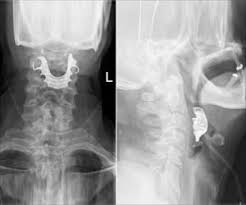

What Does Throat Cancer Look Like On An X Ray - Dysphagia The Oral Cancer Foundation / And by the time matthew's ameloblastoma was detected, his tumor was the size of a golf ball.. The most sensitive way to detect throat cancer is to have an. Tumors often show up as lighter gray than the surrounding tissue. The lungs look black because they are filled with air. If this cessation of normal eating is accompanied by changes in the voice, contact your veterinarian immediately. For patients diagnosed with throat cancer, a pet/ct scan may be used to see if cancer has spread to the lymph nodes, to determine the origin of cancer when it is found in the lymph nodes first, or to check the body for the spread of cancer cells.

The cancer can also appear as a hole in the bone. Oral cancer may present as: If you notice the second tooth from the left, you can see a dark aura surrounding the tip of the root. If this cessation of normal eating is accompanied by changes in the voice, contact your veterinarian immediately. Also, would throat cancer cause a lump like this growing on the outside of the throat/neck? Later stages indicate more advanced cancer, with stage iv being the most advanced. The tumor may be any size, but it has spread to: Throat cancer refers to cancer of the voice box, vocal cords, and other parts of the throat, such as the tonsils and the oropharynx. Tumors often show up as lighter gray than the surrounding tissue. Ameloblastoma isn't the same as jaw cancer or mouth cancer, head and neck cancer, nor even a bone cancer. That is a typical sign of an infection originating. And if this isn't cancer, could anybody offer an explanation as to what would cause a sore throat and growing lump? To evaluate respiratory conditions like asthma, bronchitis, and pneumonia, heart conditions, broken ribs, and to look for fluid and tumors within the chest cavity.

Laryngeal Cancer Latest News And Research Updates from www.medindia.net For patients diagnosed with throat cancer, a pet/ct scan may be used to see if cancer has spread to the lymph nodes, to determine the origin of cancer when it is found in the lymph nodes first, or to check the body for the spread of cancer cells. By the way i have also lost around 70lbs in the past year but i have been on a diet since the start of 2015 so hopefully this was down to. Treatment of throat cancer is based on its location, type of cancer, stage, and your child's health status. The appearance of throat cancer on the other hand depends on the part of the throat that is affected by cancer and the stage of its development. Ultrasound is useful in a few instances. The cancer can also appear as a hole in the bone. If the fna shows cancer, the pathologist (the doctor examining the samples) can often tell what type of cancer it is. Throat cancer refers cancer that develops in your throat (pharynx) or voice box (larynx).

X Ray Of The Soft Tissue Neck Lateral View Showing The Mass Arrow Download Scientific Diagram from www.researchgate.net If the cancer cells look like they might have come from the larynx or hypopharynx, an endoscopic exam and biopsy of these areas will be needed. The appearance of throat cancer on the other hand depends on the part of the throat that is affected by cancer and the stage of its development. Surgical complications and side effects arising out of throat cancer treatment. Patches of rough, white, or red tissue. Treatment of throat cancer is based on its location, type of cancer, stage, and your child's health status. Throat cancer refers cancer that develops in your throat (pharynx) or voice box (larynx). Growths of tissue on the roof of. That is a typical sign of an infection originating.